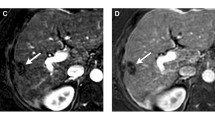

Following treatment with LRT, it is important to provide accurate treatment response assessment to help guide clinical management. The imaging appearance of HCC following LRT depends on type of LRT and is distinct for each treatment modality. In general, complete loss of APHE is suggestive of nonviable disease. However, post-treatment imaging evaluation is complicated after radiation-based therapies, in which there can be intra-tumoral APHE or nodular or geographic peri-tumoral enhancement that can persist for up to 1 year after therapy and often longer [55••, 56]. Thus, it is imperative to be aware of the different types of LRTs, as well as their expected post-treatment imaging appearance. HCC response assessment can be performed according to various response assessment guidelines, such as the European Association for the Study of Liver Disease (EASL) [57] and modified Response Evaluation Criteria in Solid Tumors (mRECIST) [58], which are patient-level response systems. Alternatively, LI-RADS TRA [45••] can be used to assess response on a per-lesion level.

While tumor response assessment after thermal ablation and nonradiation intra-arterial therapy seems relatively straight-forward, HCC treated with radiation-based therapies have a unique and complex post-treatment imaging appearance and thus categorization based on LI-RADS TRA is much more challenging. There is limited data on radiologic-pathologic correlation following radiation-based therapy using LI-RADS TRA. Mendiratta-Lala et al. [55••] evaluated 10 stereotactic body radiation (SBRT)-treated HCC, in which all tumors were necrotic on explant pathology at 12 months, out of which 40% exhibited persistent APHE and 90% exhibited WO on imaging prior to transplant. Although only a very small cohort, this study suggests that persistent arterial enhancement post-SBRT can be an expected post-treatment imaging finding. Further radiology–pathology studies in HCC treated with SBRT will be needed in order to validate the application of the LI-RADS TRA.